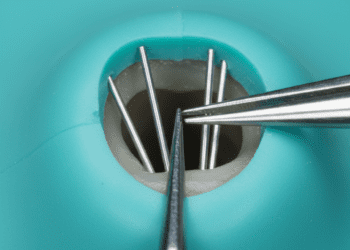

Um dos aspectos mais importantes é o nível de detalhe radiográfico da imagem. Altos níveis de detalhe permitem que professionals identifiquem pequenas fraturas, cáries incipientes e outras anomalias que poderiam passar despercebidas em imagens de menor qualidade. Para isso, é crucial que a tecnologia utilizada seja de ponta e que a técnica de exposição seja ajustada corretamente.

Para determinar se uma radiografia é de qualidade, os profissionais podem avaliar alguns aspectos técnicos. Verifique se a imagem é livre de artefatos, que podem distorcer a visualização. Imagens nítidas, com definição clara das bordas, são essenciais. Além disso, a localização correta das estruturas anatômicas é crucial. Por exemplo, elementos como raízes dentárias e seios maxilares devem aparecer de forma adequada. Uma radiografia bem posicionada irá contribuir para um diagnóstico mais assertivo.